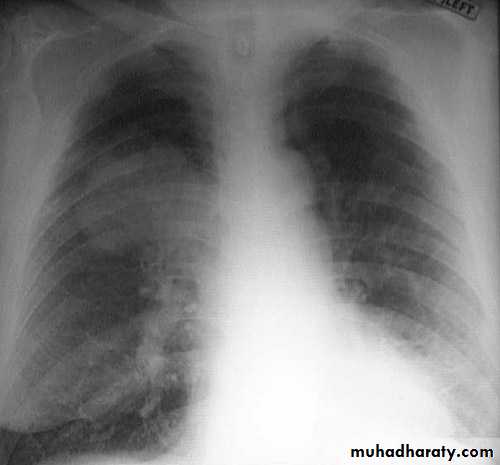

History and examinationRadiology

The prognosis of lung cancer is dismal: the 5-year survival rate for all stages of lung cancer combined is about 14%; even patients with disease localized to the lung have a 5-year survival of approximately 45%.SCC: relative good - slow growing and often resectable.

Adenocarcinoma: poor, because most tumors do not present signs of airway obstruction (because of there peripheral location) and therefore are highly advanced before presentation; bronchioloalveolar carcinoma has a good prognosis.